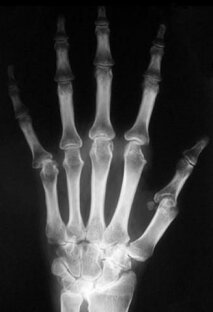

Реактивный или ревматоидный ? Вот в чем вопрос😁 Если вы меня потеряли, дорогие, - я здесь опять. Если не теряли - тоже хорошо. Коротко отчитываюсь про " чем лечили ". Хирург назначил на 14 дней гормоны: 3 дня было улучшение, далее - никак🙄 Движения в кистях и пальцах также ограничено. По ходу зацепила 👑 Суставы отекли, распухли, болели ещё больше. Опрометчиво на мероприятие решила пойти в кольце, пришлось снимать с трудом через три часа. 🌿С нутрициологом Асей продолжаем дальше Скайп-консультации: диета противовоспалительная продолжается, я уже втягиваюсь). Один день в неделю сделали разгрузочным от диеты, с большим удовольствием хомячила 5% домашний творожок...